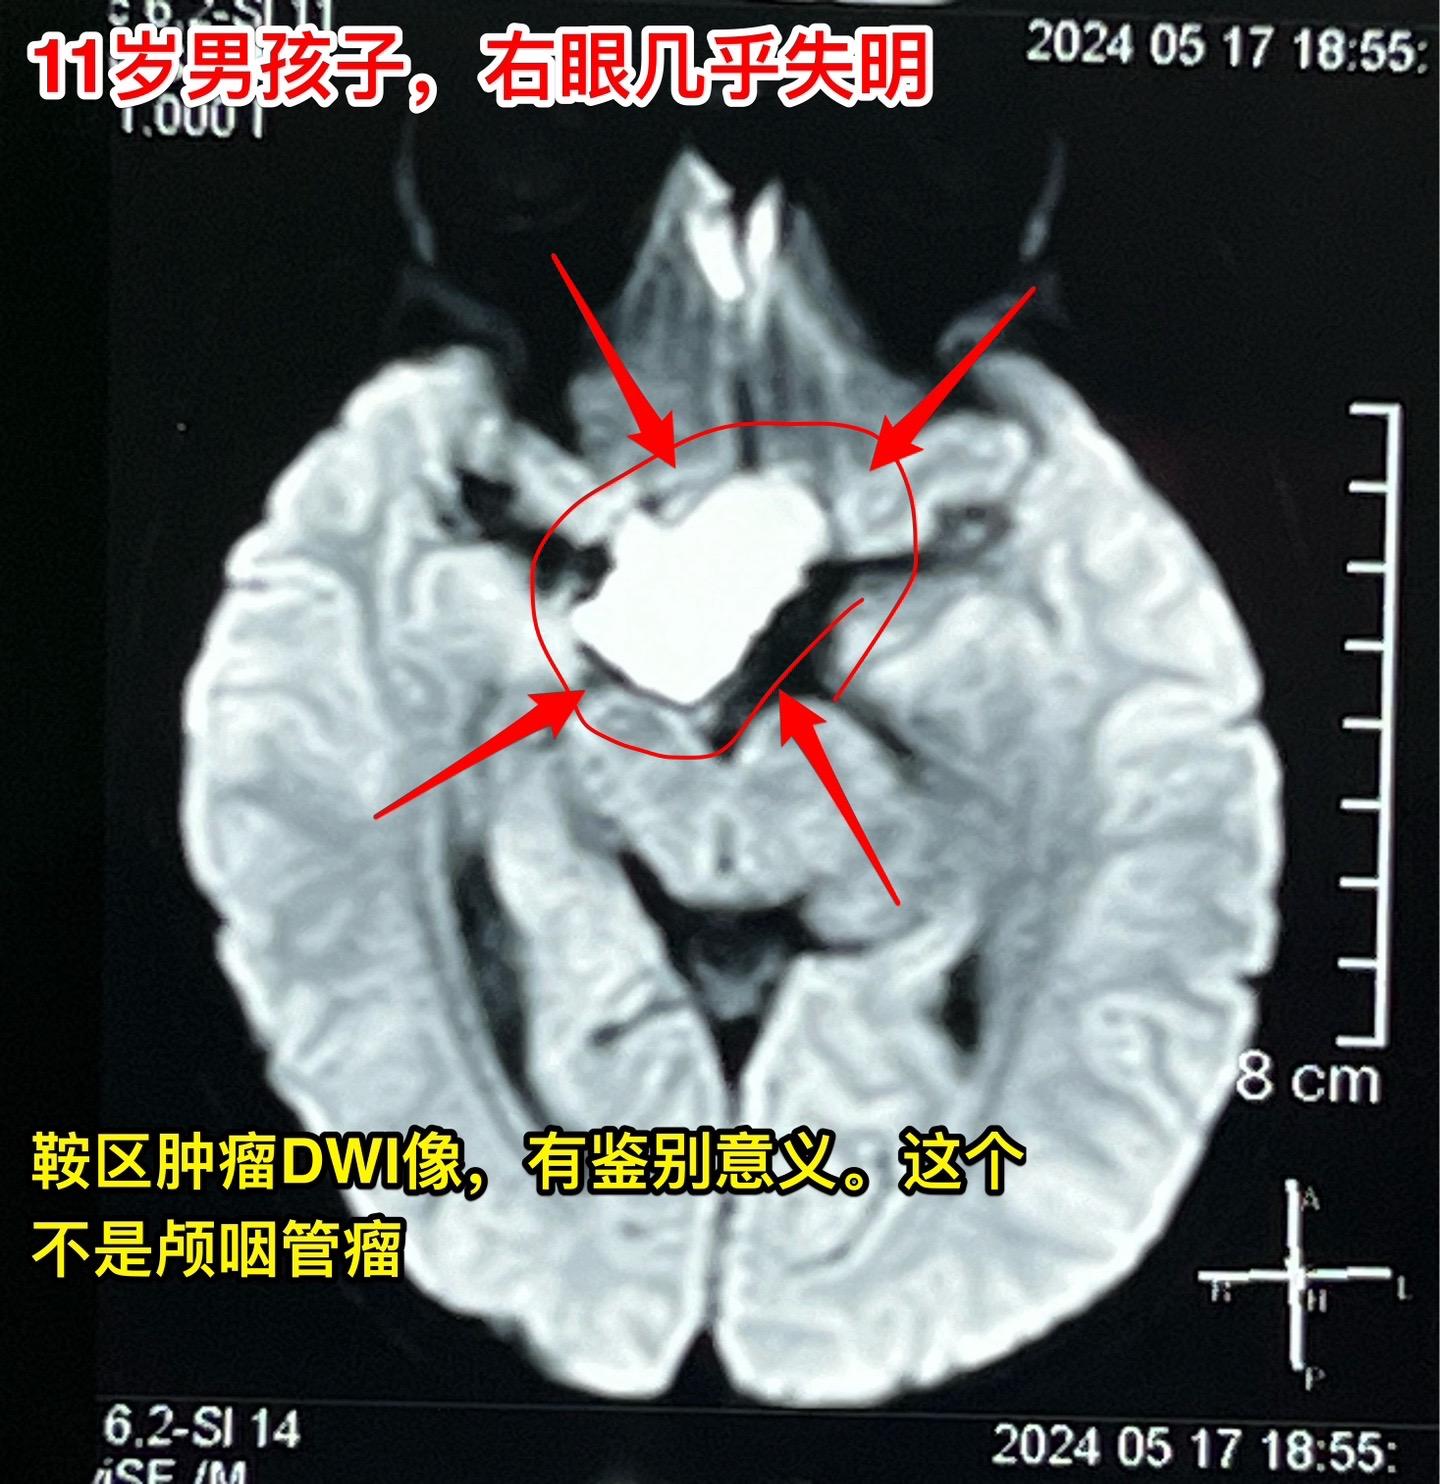

鞍区皮样囊肿比颅咽管瘤更罕见。11岁的湖北男孩子在学校体检查视力发现右眼几乎失明了,看不见东西,只有光感! 而他自己却不知道!平时也没有感到头痛,没有太多的不适。这个孩子是多粗心呀! 随后行脑部CT和磁共振检查发现鞍区 有个肿瘤,怀疑为颅咽管瘤。CT显示肿瘤没有钙化,这一点不符合颅咽管瘤。 5月31日作了开颅手术,将病灶完全切除。病灶的囊皮是灰色的,内部有油脂样的粘滞物,还含有毛发。所以术中诊断为皮样囊肿。这是近10年以来的第三例鞍区皮样囊肿手术。前两例